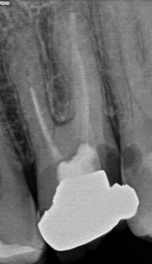

Conservative access prep?

Has the dentist drilled the small hole needed, or a much bigger hole than is typically required? A bigger hole not only damages your tooth more, it also increases your risk of future problems.